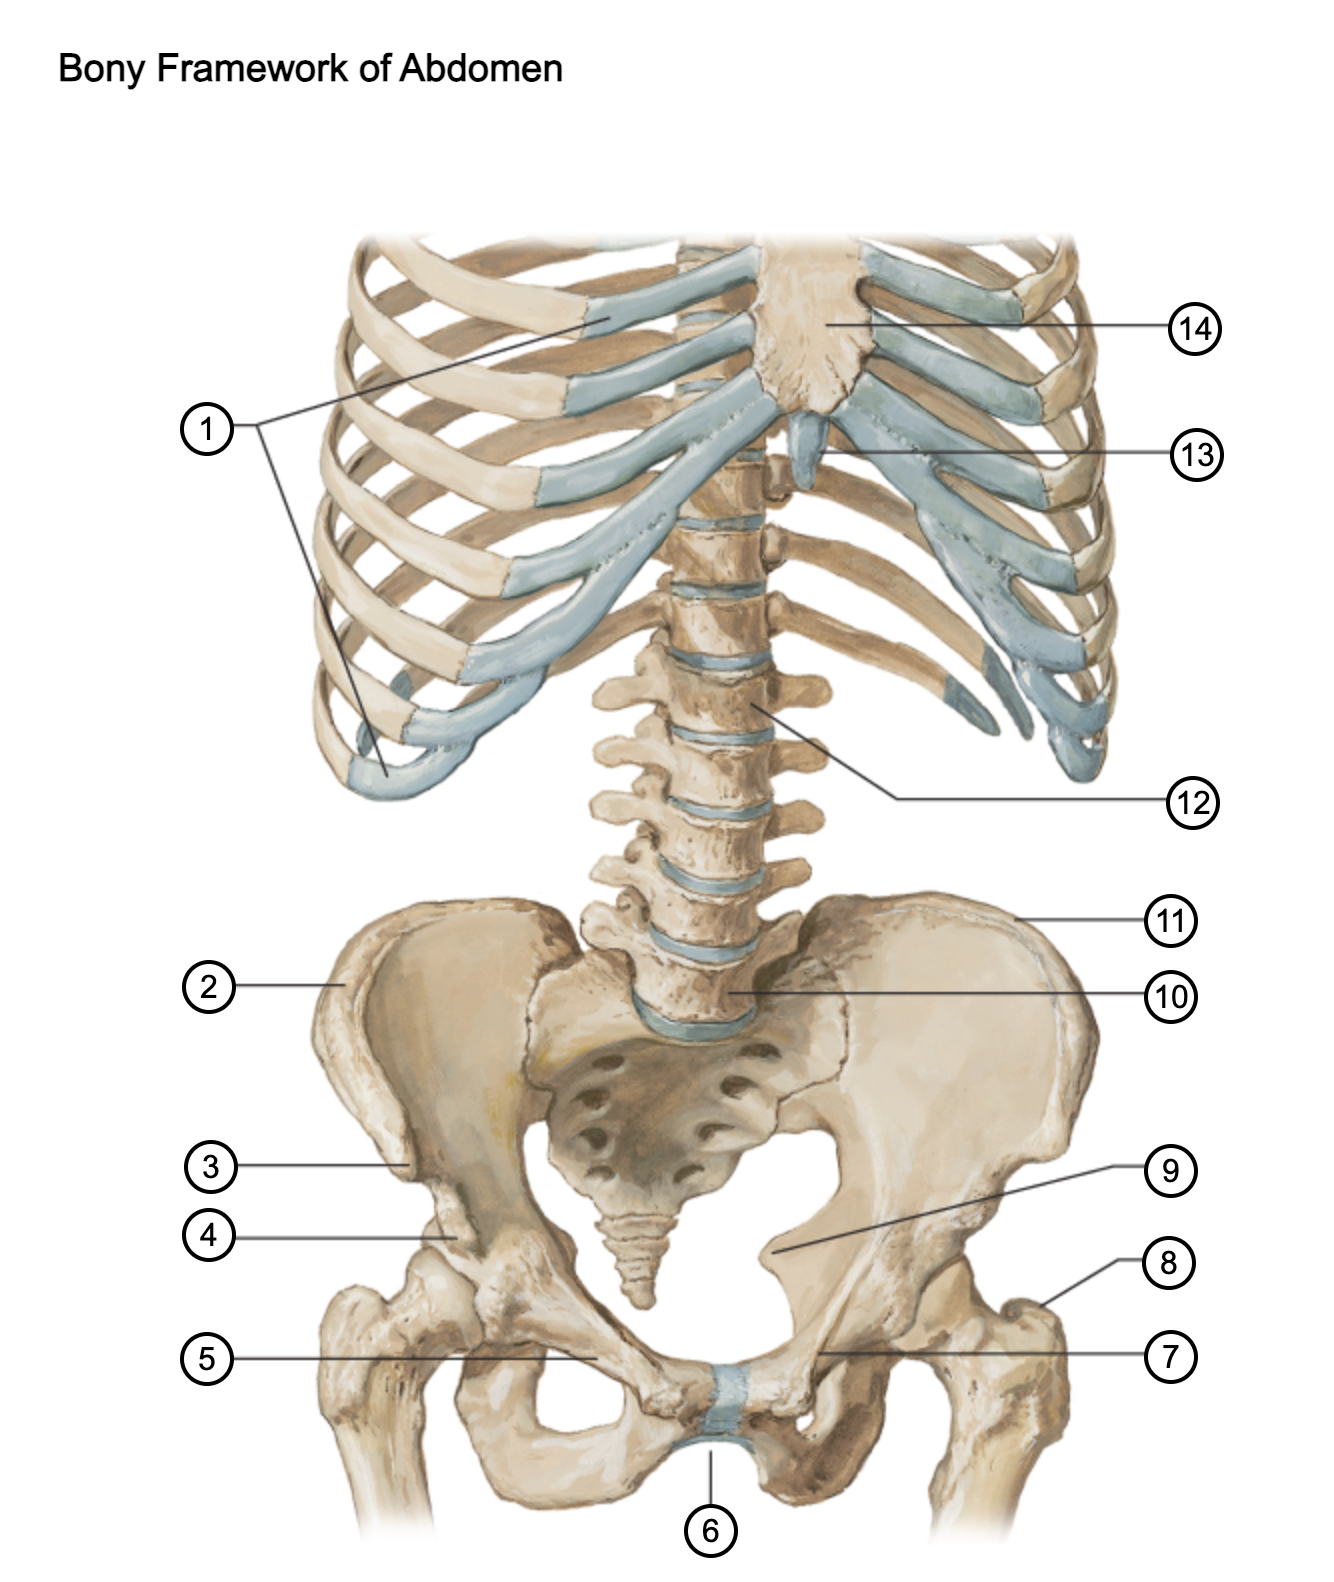

1

costal cartilages

2

iliac crest

3

anterior superior iliac spine

4

anterior inferior iliac spine

5

superior pubic ramus

6

pubic arch

7

pecten pubis

8

greater trochanter

9

ischial spine

10

L5 vertebra

11

iliac crest

12

L1 vertebra

13

xiphoid process

14

body of sternum